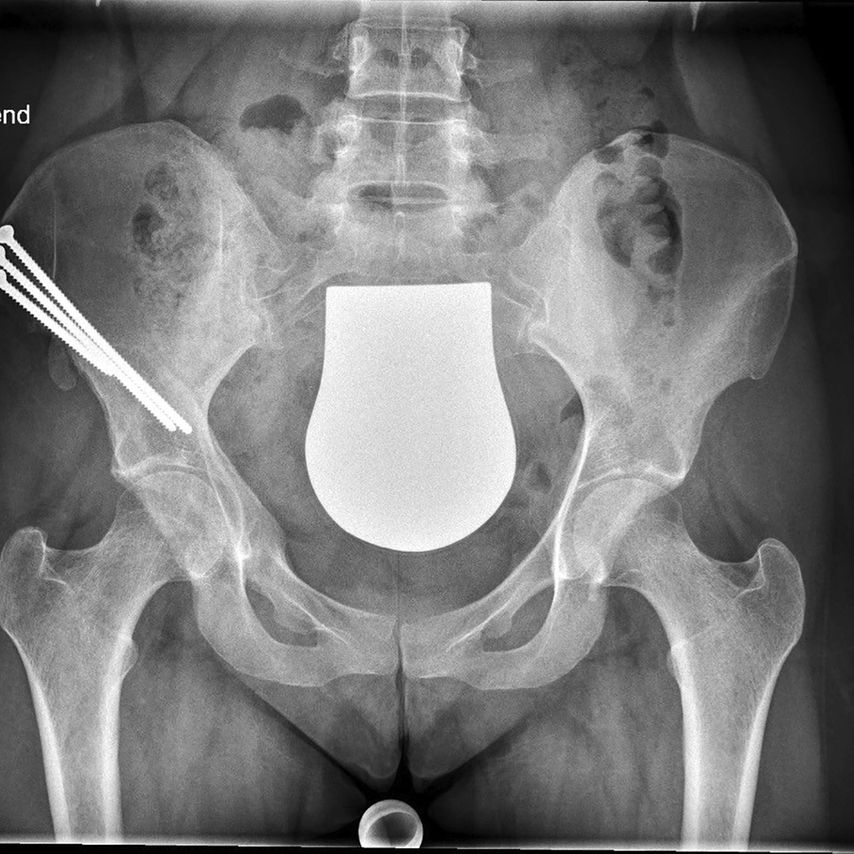

Die periacetabuläre Beckenosteotomie (PAO) nach Ganz hat sich seit der Erstpublikation 19881 zu einem etablierten Verfahren in der rekonstruktiven Beckenchirurgie entwickelt. Bei der PAO wird die Hüftgelenkspfanne chirurgisch ausgeschnitten, um in der Folge vollkommen mobil, mit der Hüftkopfmitte als Drehzentrum, in einer korrigierten Position mit dem Becken neu fixiert zu werden. Das Verfahren erlaubt eine bessere Primärstabilität gegenüber der Triple-Beckenosteotomie, da der hintere Beckenpfeiler nicht durchtrennt wird und die Integrität des Beckenrings somit intakt bleibt. Eine Fixierung der Osteotomie mit Schrauben erlaubt unmittelbar postoperativ eine Übungsstabilität. Eine Gipsruhigstellung wie bei der Triple-Beckenosteotomie ist in der Regel nicht erforderlich. In der Rehabilitationsphase ist eine Gewichtsbelastung der Hüfte in der Regel nach 6 Wochen schrittweise möglich.

Die vier Teilosteotomien der PAO – erstens mit dem inkompletten Ischium-Schnitt distal des Acetabulums, zweitens mit der kompletten Osteotomie des oberen Schambeinastes, drittens mit dem inkompletten Schnitt durch die Ilium-Schaufel proximal der Gelenkspfanne und viertens mit dem finalen Verbindungsschnitt medial und posterior des Acetabulums – können über einen einzigen Hautschnitt von ventral durchgeführt werden. Dieser OP-Zugang verlangt aber nach Spezialinstrumenten und speziell geformten Meißeln. Erschwerend kommen bei jeder PAO-Technik die variablen anatomischen Verhältnisse des knöchernen Beckens und die Nähe zu den großen Beckengefäßen und Nerven hinzu. Das chirurgische Verfahren ist somit generell anspruchsvoll und mit einer flachen Lernkurve verbunden.4 Die PAO wird daher nur an Zentren mit Erfahrungen in der gelenkserhaltenden Beckenchirurgie und dementsprechenden Fallzahlen angeboten und ist kein orthopädischer Standardeingriff.

Intraoperative Bildgebung als Fehlerquelle hinsichtlich der Pfannenversion

Die intraoperative Reorientierungs-Position des Pfannenfragmentes auf Basis von Durchleuchtungsbildern in liegender Position stellt derzeit immer noch eine große Herausforderung für jeden Chirurgen dar. Die Ursachen dafür liegen einerseits in der posterior-anterioren Röntgenstrahlrichtung und der geringen Film-Fokus-Distanz der intraoperativen Durchleuchtung im Vergleich zur konventionellen Beckenröntgenaufnahme, andererseits in einer veränderten Beckenkippung im Liegen im Vergleich zur stehenden Position. Diese Faktoren verändern die Darstellung der Pfannenversion intraoperativ. Da aber sowohl eine Unter- als auch eine Überkorrektur der Pfannenversion zu klinisch schlechteren Ergebnissen und in der Folge zu einer erhöhten Arthroserate führt, ist auf die Pfannenversion besonders zu achten.5 Die Verwendung von Schnitt- und Korrekturblöcken könnte hier zukünftig Abhilfe schaffen.

Intraoperative Schnittblöcke als chirurgische Hilfestellung

Die Verwendung einer patientenspezifischen Instrumentation (PSI) auf Basis einer 3D-Modell-Planung ist bei knienahen Umstellungsosteotomien in der Orthopädie bereits ein gängiges Verfahren. Dieses Konzept kann nun teilweise auch bei der PAO angewendet werden. Dabei wird das knöcherne Becken präoperativ in der Computertomografie erfasst und am 3D-Modell werden die optimalen Schnittführungen um die Hüftgelenkspfanne geplant. Mittels eigener Software kann das Acetabulum am Monitor auf ein Grad genau in allen Ebenen gedreht werden. Auch eine notwendige Translation des Fragments kann beurteilt werden. In der Korrekturposition des Pfannenfragments können zusätzlich bereits die Positionen und Längen der Schrauben errechnet werden. Auf Basis dieser Planung werden PSI-Schnittblöcke und Korrekturblöcke produziert und für den Eingriff sterilisiert.

Bis jetzt gibt es zu dieser Thematik nur allgemeine anekdotische Berichte in der Literatur.6 Erste intraoperative Anwendungen von PSI-Schnittblöcken für die PAO an unserer Abteilung waren aber vielversprechend. Natürlich verlangt das Anlegen von Schnittblöcken und Korrekturblöcken mehr Weichteilrelease von den knöchernen Strukturen und unter Umständen auch einen längeren Hautschnitt mit größeren Expositionsflächen am Becken. Zudem haben wir bisher aufgrund unseres alleinigen OP-Zugangs von ventral nur Schnittblöcke für die Ilium-Osteotomie und den proximalen Anteil des Verbindungsschnittes verwendet. Eine exakte Schnittplanung in dieser Region ist aber wichtig, um hier nach vollständiger Mobilisierung des Pfannenfragments den Korrekturblock exakt so zu positionieren, dass sich das Pfannenfragment in der gewünschten Abduktions-, Flexions- und Rotationsstellung einstellen lässt. In dieser Position können über die vorgefertigten Bohrhülsen im Korrekturblock gleich die Schraubenkanäle vorgebohrt werden. Eine zeitliche Verzögerung durch die Verwendung der Schnittblöcke konnten wir insgesamt nicht beobachten.